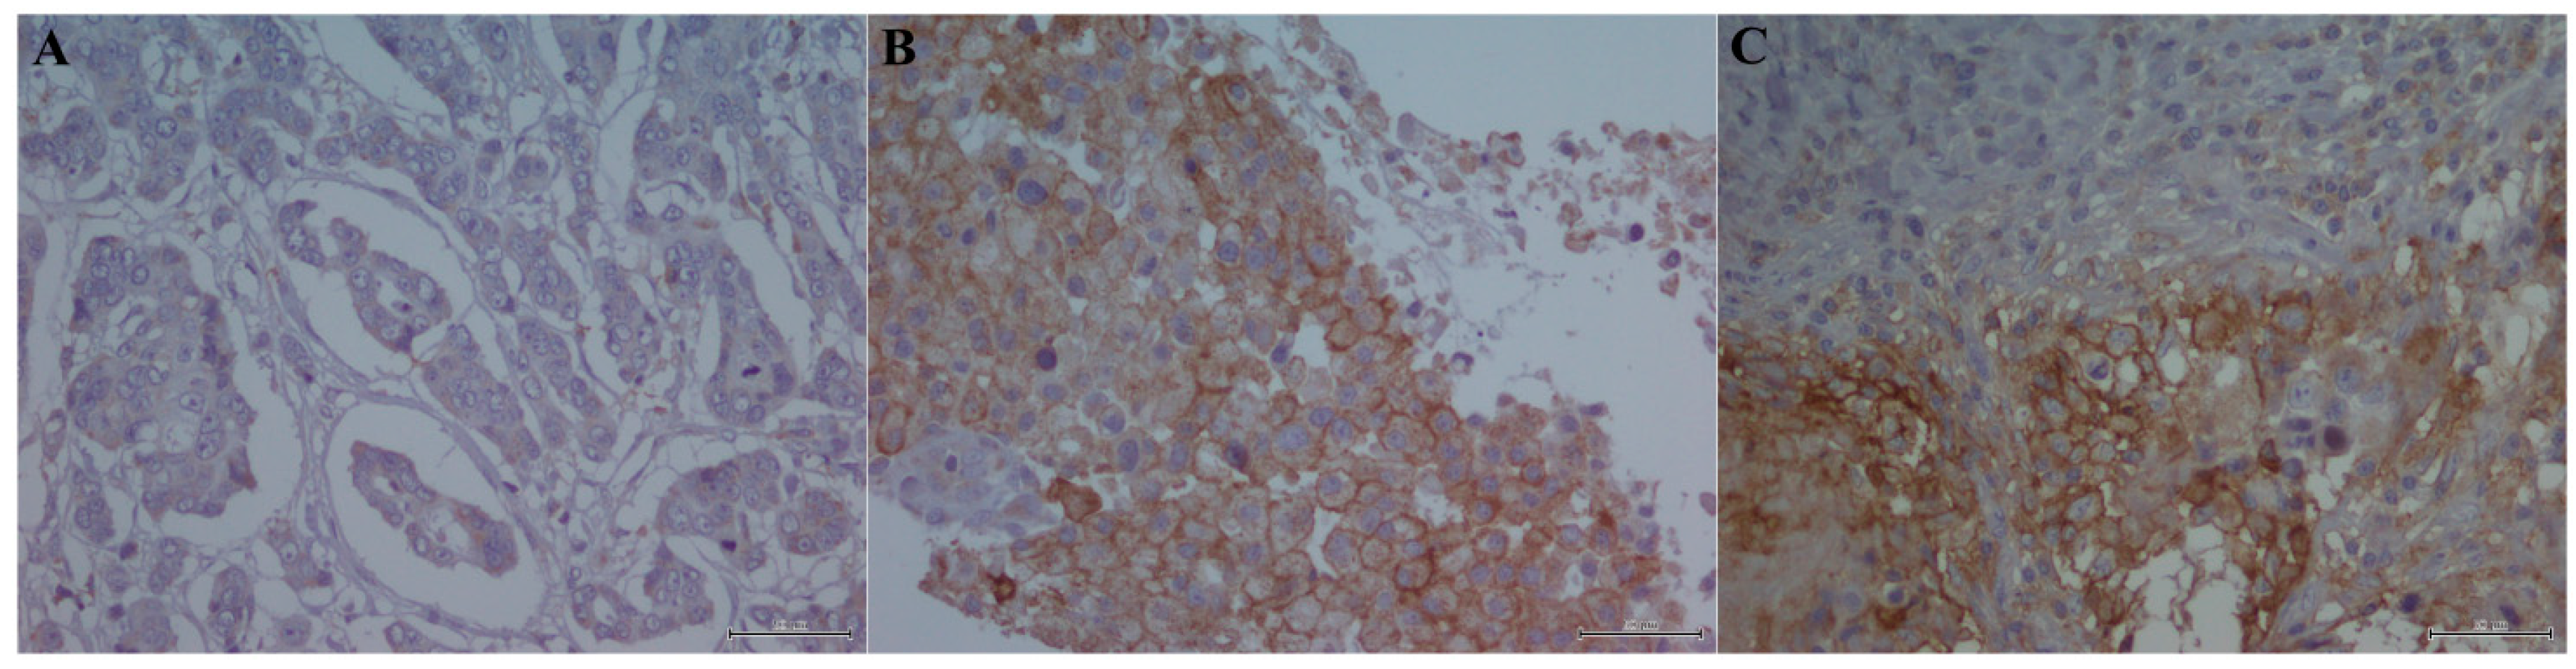

4.3. Immunohistochemistry Analysis

4.4. Evaluation of Immunohistochemistry on TIL and Tumor Cells

- Scognamiglio, G.; de Chiara, A.; di Bonito, M.; Tatangelo, F.; Losito, N.S.; Anniciello, A.; de Cecio, R.; D’Alterio, C.; Scala, S.; Cantile, M.; et al. Variability in immunohistochemical detection of programmed death ligand 1 (PD-L1) in cancer tissue types. Int. J. Mol. Sci. 2016, 17, 790. [Google Scholar] [CrossRef] [PubMed]